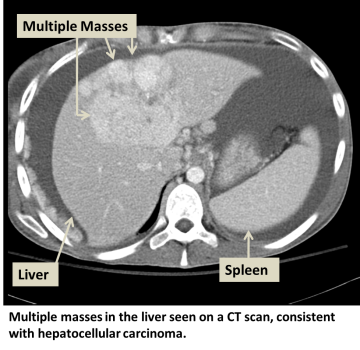

Hepatocellular carcinoma (HCC) is the most common type of primary liver cancer. Primary liver cancer refers to cancer that originates in the liver rather than cancers from other organs that metastasize to the liver (see metastatic liver cancer). HCC can start as a single tumor or as several tumor nodules across the liver.

In addition to a physical examination, laboratory tests and imaging studies may be needed. These tests may also be necessary at regular intervals to detect early cancer if certain risk factors are present. Our physicians may enroll you into such a screening or surveillance program. The tests may include:

- CT scan